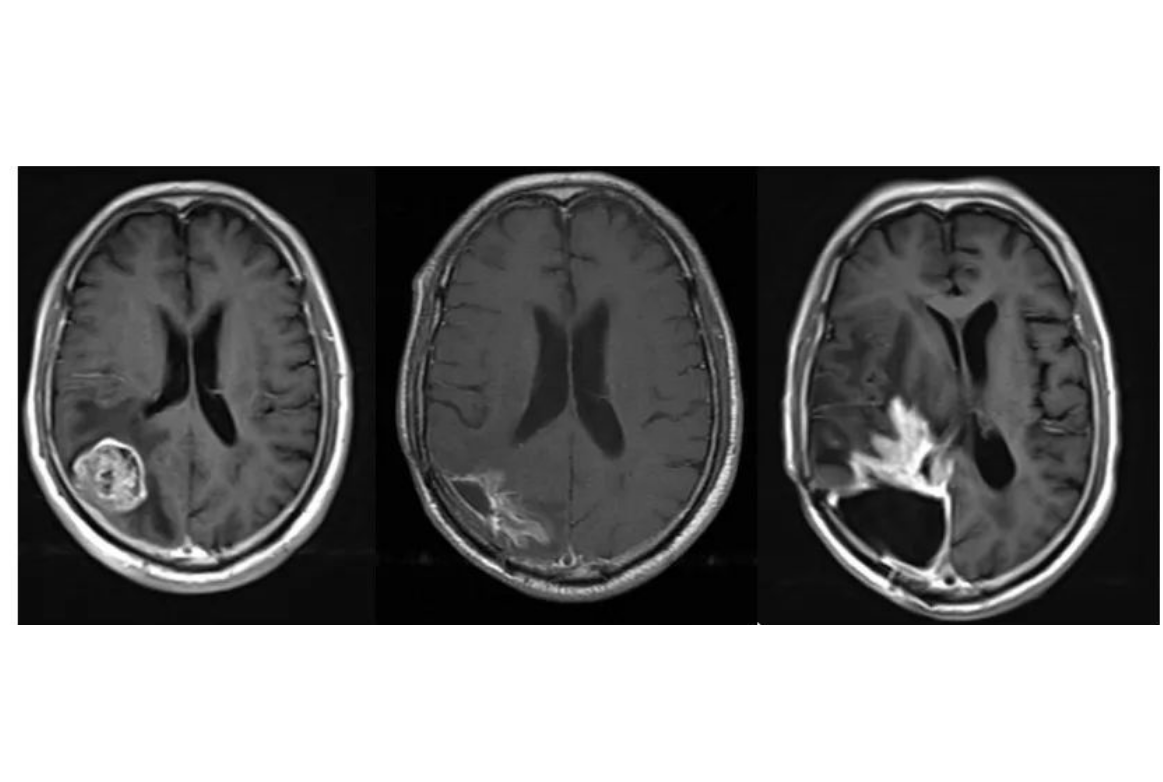

1.磁共振增强:放化疗后可导致血管内皮细胞损伤、坏死,造成血管内皮细胞紧密连接损害,BBB功能损害、通透性增强,在MR增强强化。MR增强上出现强化灶、新强化灶。类似肿瘤复发的影像学表现。胶质母细胞瘤放疗后,MR增强强化见于:70%:肿瘤复发、坏死(结节或多发强化区,术后3月后);30%:单侧放射性坏死(地图样强化)。

肿瘤复发:多发病灶沿白质纤维束播散、累及胼胝体

3.坏死期:脑组织病灶局部出现坏死,可伴有出血或渗血,头颅MRI显示信号不均,增强扫描可见强化。

4.囊变期:患者头颅MRI显示放射性脑损伤病灶边界清晰并囊性变,信号接近游离水信号,有或无占位效应。囊变期病灶可较长时间稳定,但也可能急性增大,引起脑疝,患者出现意识水平下降,昏迷甚至死亡。